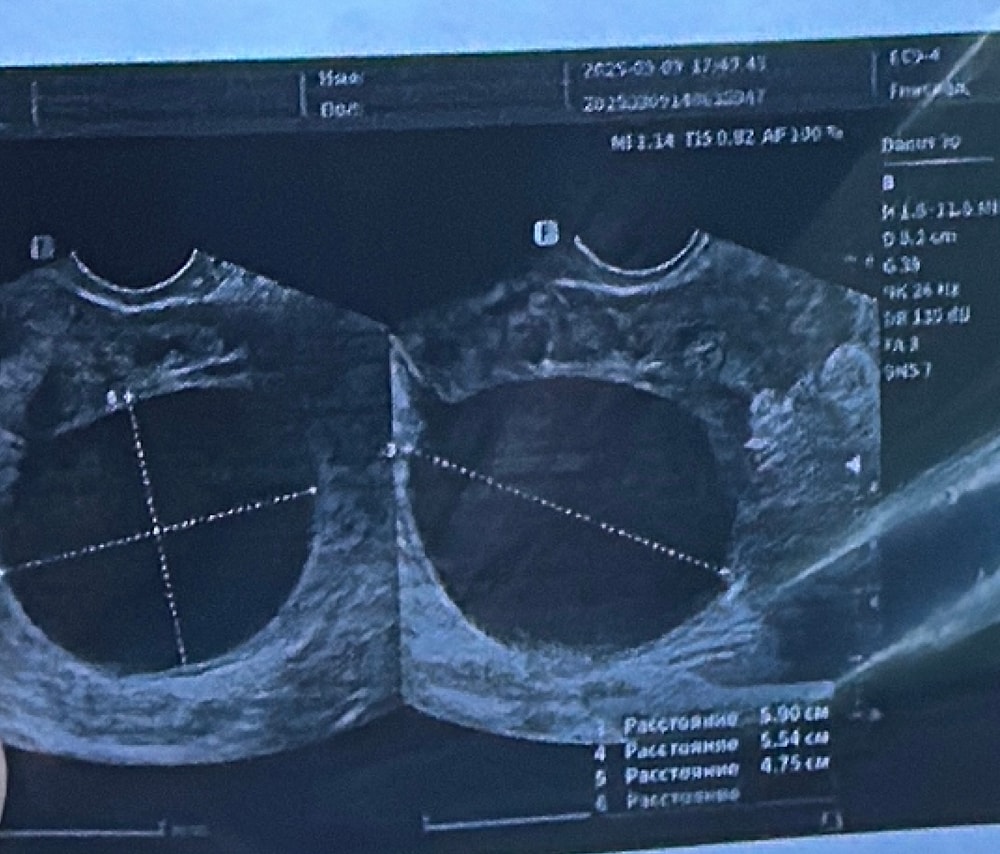

Katerina, Изображение

09.09.2025

у меня была фолликулярная киста по узи (300 мл). решили делать лапаро, во время которой выяснилось, что под жидкостью скрывалась дермоидная киста. Вам делали что-то кроме узи?

Anna, нет , еще ничего , только сделала узи , завтра к врачу